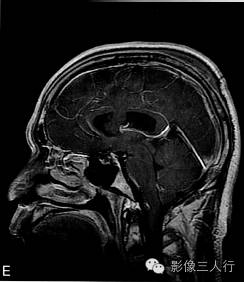

A.T2WI横断面;B.T1WI横断面;CFLAIR冠状面;D、E、F.增强横断面、矢状面、冠状面;G、H.CT平扫、增强;I.HE×100

肿瘤呈类圆形,边界清楚,位于左侧脑室前角及室间孔区,左侧脑室前角、三角部及左侧脑室后角扩张积水。MRI平扫T2WI(图A)肿瘤呈稍高信号,内见小范围高信号区;T1WI(图B)肿瘤呈等信号,内见低信号区;冠状面水抑制相(图C)肿瘤呈稍尚信号,内部原长T1长T2区信号呈低信号;增强扫描(图D~F)肿瘤强化不明显;CT平扫(图G)左侧脑室前角类圆形、边界清楚、较均匀等密度肿块,增强扫描(图H)强化不明显。